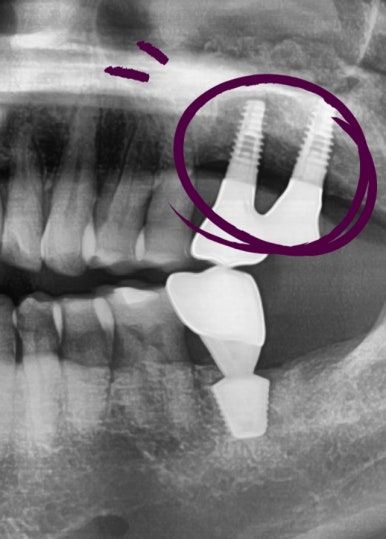

간단한 상악동 수술이 아니라 복잡한 고난이도의 상악동 수술이 필요했는데

상악동을 들어올려 뼈이식을 하고(노란색으로 표시된 부분)

임플란트 2개를 심은 모습입니다. [②로 표시된 부분]

나머지 ①③ 표시된 부분도 원장님께 임플란트 수술을 받으셨습니다.

④로 표시된 부분은 사랑니 발치한 부분입니다.